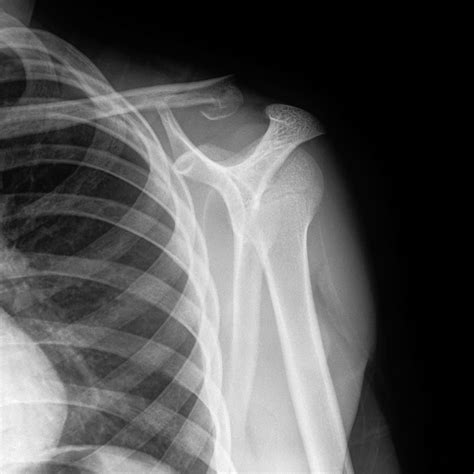

Interpreting the Results: What “Normal” Really Means

It is important to understand that a report stating “no acute osseous abnormality” is the medical equivalent of a Normal Shoulder Xray. This means the bones appear intact, aligned, and free of degenerative changes. However, patients often feel frustrated if they are still in pain despite having a “normal” scan. This occurs because the shoulder’s function depends heavily on muscles and tendons—the soft tissues—that an X-ray simply cannot see.

If your results are normal but your pain persists, your doctor may suggest a physical therapy evaluation. Often, pain originates from muscle imbalances, poor scapular mechanics, or nerve irritation, none of which will alter the appearance of your bones on a radiograph. Always ensure your physical exam findings are correlated with the radiological report.

Advancing Toward a Diagnosis

If the radiograph confirms your shoulder structure is normal, the diagnostic journey usually follows a logical path. Your provider will likely perform a series of orthopedic stress tests to isolate the specific tendon or ligament in distress. By ruling out bone fractures or dislocations early, your healthcare team saves time and resources. If the pain remains unexplained, an ultrasound or an MRI (Magnetic Resonance Imaging) might be ordered to get a high-resolution view of the rotator cuff muscles, which are the most common source of persistent shoulder dysfunction.

In summary, the role of a standard shoulder radiograph is to act as a definitive gatekeeper. By focusing on the structural integrity of the bones and the alignment of the joints, it provides the necessary confidence to either proceed with conservative management like physical therapy or to escalate to more advanced imaging techniques if soft tissue damage is suspected. Relying on this initial baseline ensures that you receive a targeted, efficient, and accurate medical plan for your recovery.